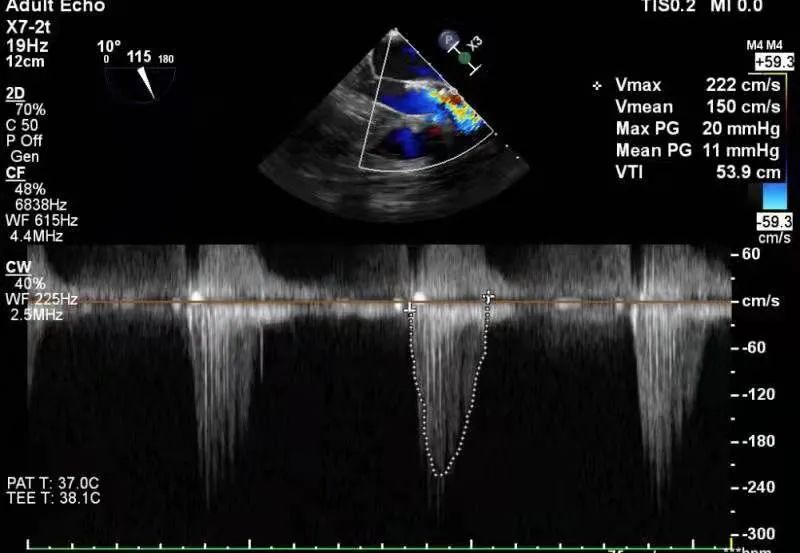

术前、术后患者跨瓣压差对比

考虑患者窦部结构较小,为避免发生冠脉风险,选择不予以后扩。超声提示患者跨瓣压差即刻显著下降,反流量较术前明显改善。术中未出现相关并发症,术后患者心功能持续得到改善,效果良好,圆满取得此次手术成功。

心超:主动脉退变伴重度狭窄,轻、中度反流,瓣上最大流速4.1m/s,平均压差42mmHg。